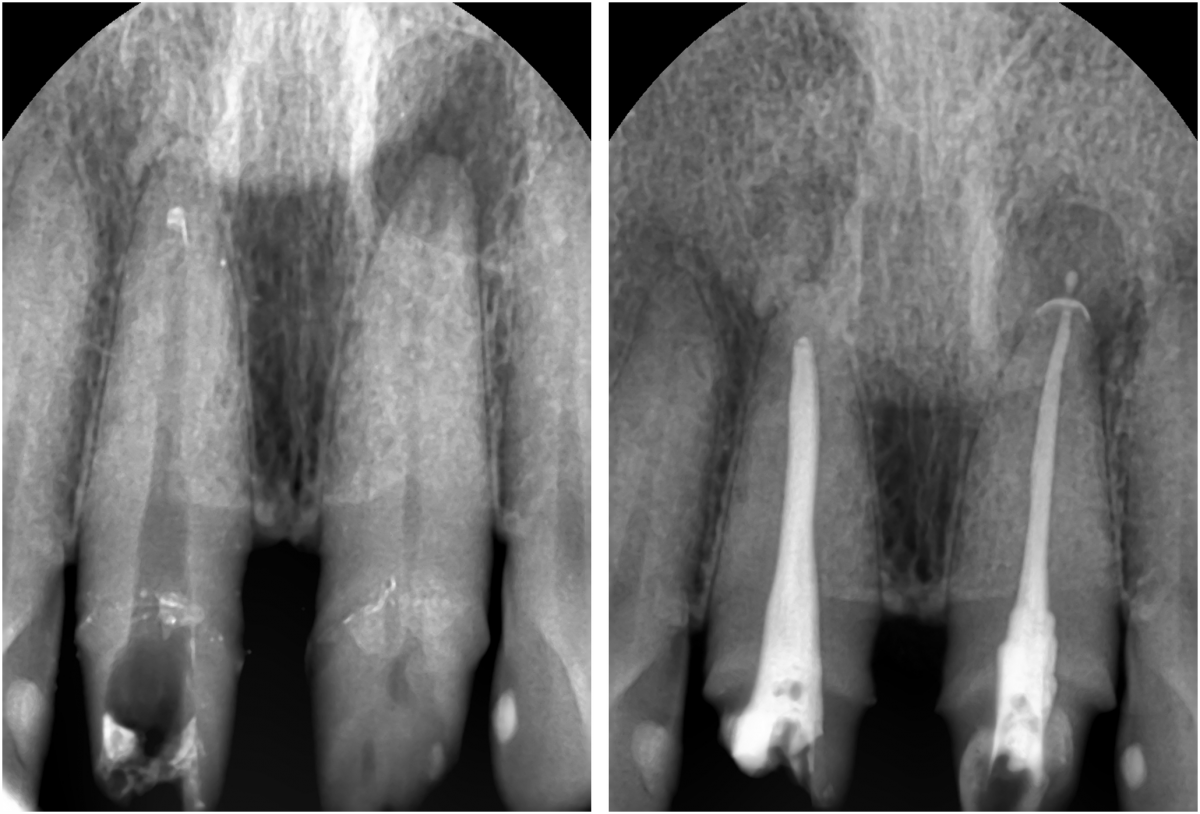

Apicorctomy /central incisor /GBR ; 6-year follow up.

<CJ SBN> Apicorctomy /central incisor /GBR ; 6-year follow up.

▲CBCT. Left central incisor had a apical lesion.